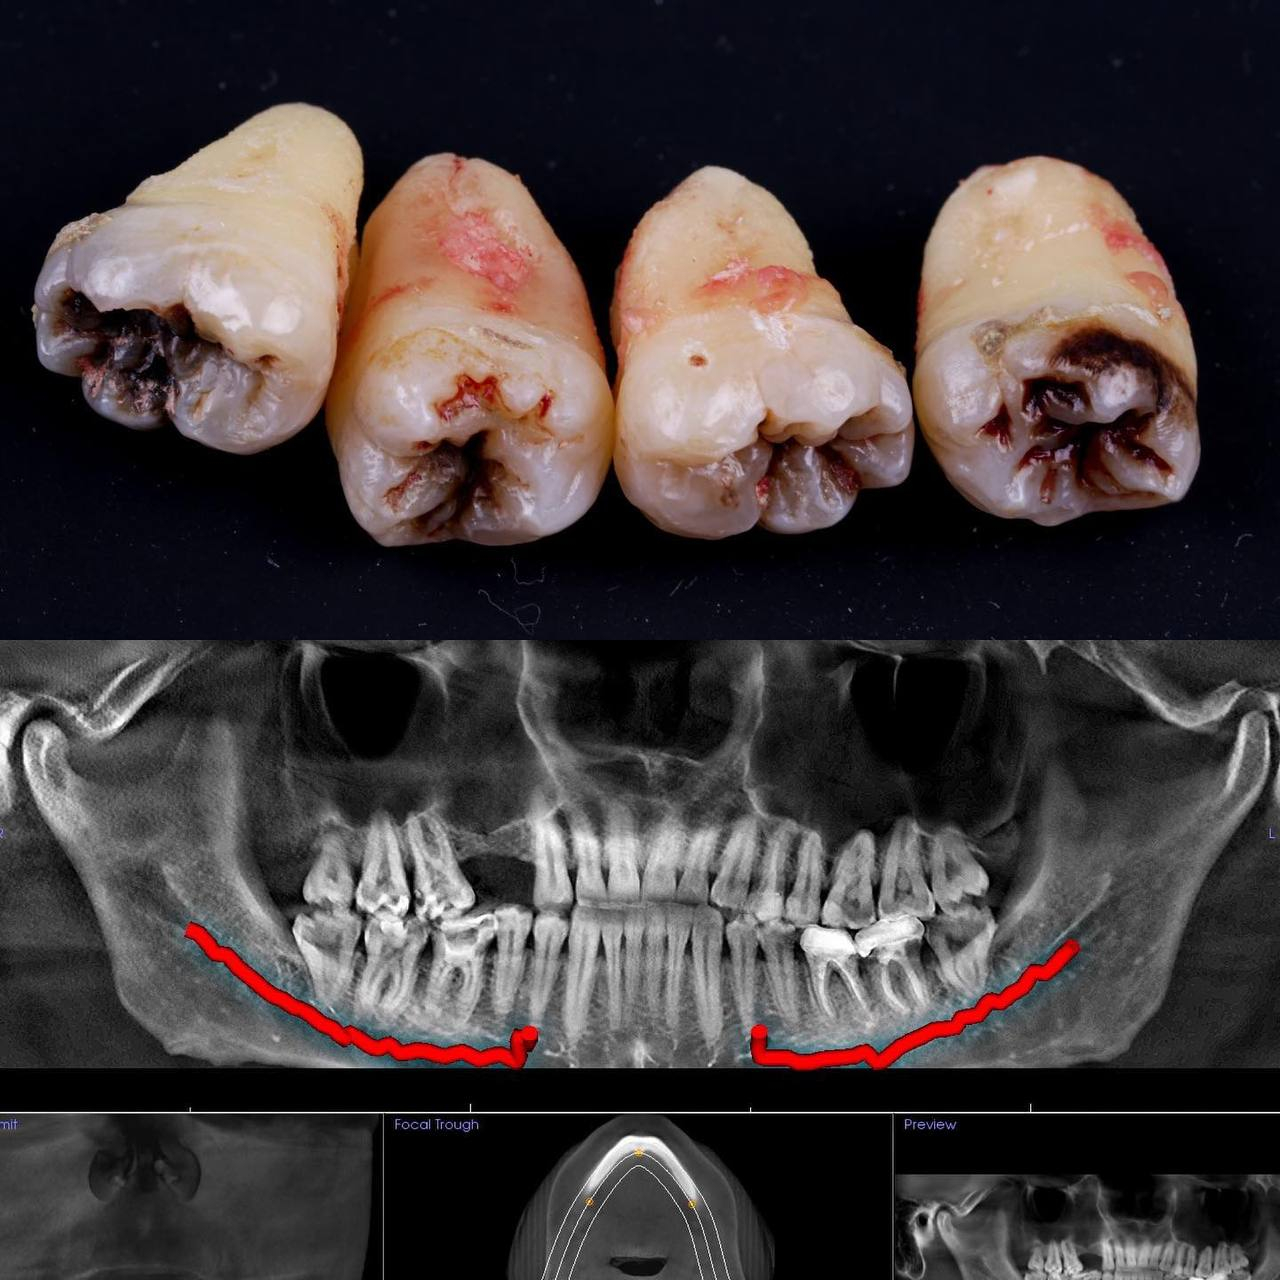

Видаляти зуб мудрості рекомендується тоді, коли він давить на зубний ряд та посуває інші зуби, завдає болю або сам вже пошкоджений карієсом.

Показання до проведення процедури видалення крайніх молярів

- Відсутність місця у зубному ряду. Коли зубний ряд вже укомплектований, прорізування вісімок деформує ряд всіх зубів у щелепі. Ти можеш помітити, що зуби були ідеально рівні, а тепер їх посуває гоноровий восьмий.

- Розвиток хвороб. Зуб потроху росте, ясна утворює над його верхівкою капюшон, туди забивається їжа, викликаючи запалення і неприємний запах. Через це також може розвинутися карієс.

- Постійні болючі відчуття. Зуби мудрості рідко ростуть рівно, частіше трохи розвертаючись в інший бік. Поступово неприємні відчуття переростають у сильний біль, який перетворює життя на випробування.

В будь-якому з цих випадків, записуйся на прийом в Космічну стоматологію Драганчука, ми скеруємо тебе на 3D комп'ютерну томографію, яка дозволить точно визначити ціни на видалення 8 зуба у Львові. Безболісне й швидке розв’язання проблеми з вісімками не за горами!